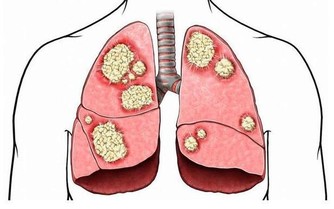

都說“胃是喇叭,肝是啞巴”。胃痛你有感覺,卻沒有人會說肝疼,但一查出肝的病,基本都是......

因為肝臟是唯一沒有痛感神經的器官,所以無論它累成怎麼樣,它也從不呻吟叫苦,也不會喊痛,這也是人們經常忽略它健康狀況的根本原因。這就是為什麼肝癌一發現,就是晚期的原因。

7個跡象預示肝出問題

肝臟“罷工”潛伏期長,病情隱蔽,尤其是中早期,往往症狀不明顯,再加上人們意識不足,治療極易被延誤。

美國《預防》雜誌網站近日總結了肝功能衰退的7個跡象,發現以下症狀應及早去醫院做進一步檢查,切莫錯失最佳治療時機。